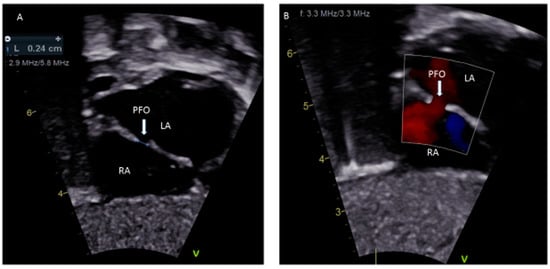

- Silvestry, F.E. Guidelines for the echocardiographic assessment of atrial septal defect and patent foramen ovale from the American Society of Echocardiography for cardiac angiography and interventions. J. Am. Soc. Echocardiogr. 2015, 28, 910–985. [Google Scholar] [CrossRef]

- Dowling, M.M.; Ikemba, C.M. Intracardiac shunting and stroke in children: A systemic review. J. Child Neurol. 2011, 26, 72–82. [Google Scholar] [CrossRef]

- Giannopoulos, A.; Gavras, C.; Sarioglu, S.; Agathagelou, F.; Kassapogelou, I.; Athanassiadou, F. Atrial septal aneurysms in childhood: Prevalence, classification, and current abnormalities. Cardiol. Young 2014, 24, 453–458. [Google Scholar] [CrossRef]